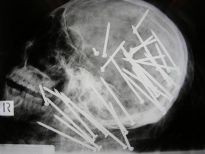

Şoke eden röntgen filmleri

Bu röntgen filmleri görenleri şaşkına çeviriyor!